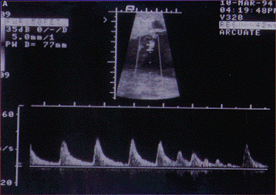

Se ha reportado un caso de taquicardia ventricular intermitente en un feto durante la gestación , cuya madre sufre de síndrome de QT largo (29) , posterior al nacimiento el bebe evidencio la presencia de QT largo. En un importante estudio Shwartz y col (30) analizaron 333034 ECG tomados entre el tercer y cuarto día de vida de recien nacidos entre los años 1976-94 para medir el QT y realizaron el seguimiento al año. Durante este período ocurrieron 34 muertes: 24 por muerte subita infantil , de los cuales 12 presentaban QTc de mayor duración que los que murieron por otras causas (435+/- 45 mseg vs 393 +/-24 mseg) o que el grupo sobreviviente (400 +/- 20 mseg) . Ninguno de los casos que sobrevivieron o que fallecieron por otras causas presentaban QT largo . El riesgo relativo de muerte súbita infantil con QTc > 440 mseg es de 41.3 (95 % intervalo confidencia 17.3 a 98.4) lo cual, es mucho más elevado que el producido por los factores clásicos como la madre fumadora. En teoría los niños con SQTL podrían beneficiarse con la administración cuidadosa de betabloqueantes. Hofbeck y col (31) sugieren que la presencia de bradicardia en un feto sin otra evidencia de patología cardíaca deberá hacer sospechar de SQTL , debiendo realizarse ECG y valoración completa familiar en estos niños.